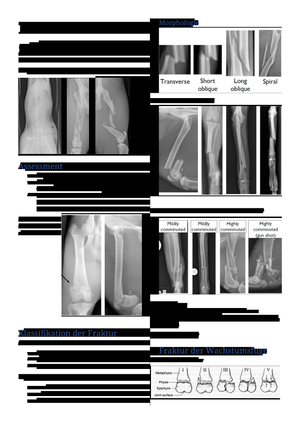

uniboard.ch Downloads Studium Universität Zürich (UZH) Vetsuisse-Fakultät UZH 2. Studienjahr Organblock Bewegungsapparat Frakturbehandlung Kleintiere (Deutsch) Frakturbehandlung Kleintiere (Deutsch)

Frakturbehandlung Kleintiere (Deutsch)